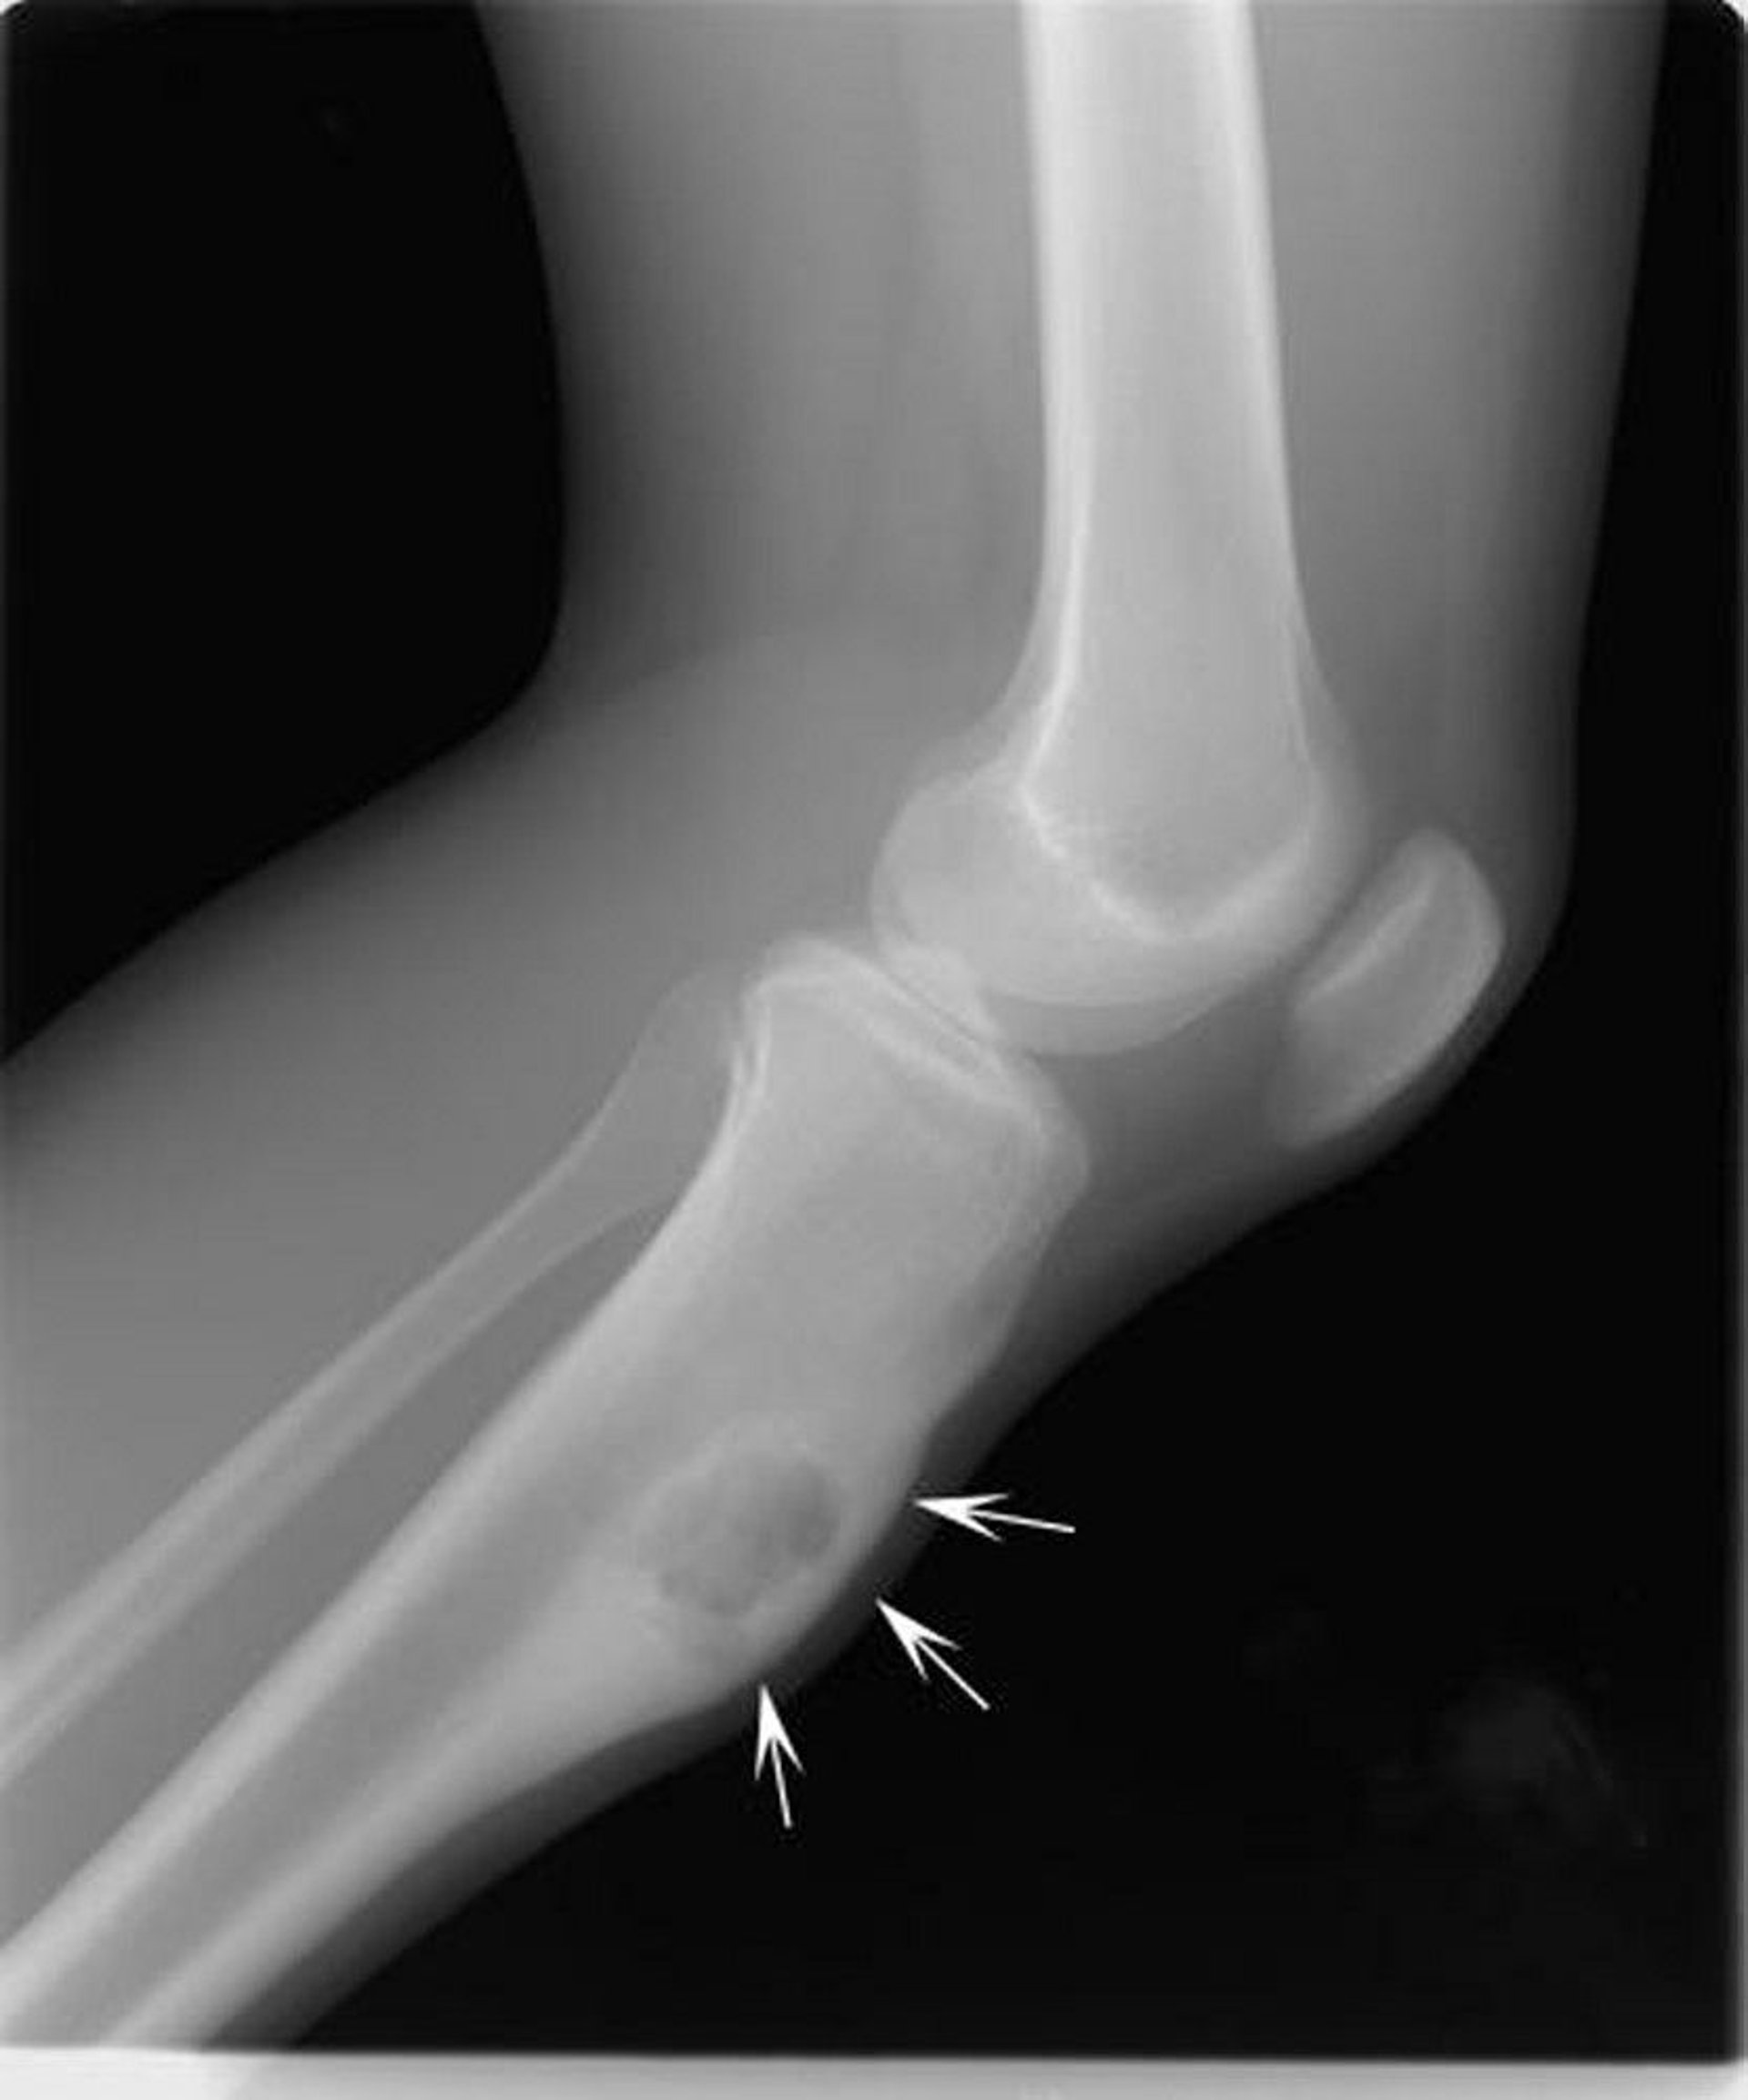

This x-ray of the knee shows a chondromyxofibroma (arrows) in the shin bone below the knee.

Image courtesy of Michael J. Joyce, MD, and Hakan Ilaslan, MD.